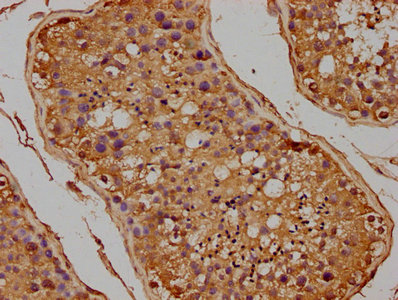

IHC image of CSB-PA008711HA01HU diluted at 1:100 and staining in paraffin-embedded human testis tissue performed on a Leica BondTM system. After dewaxing and hydration, antigen retrieval was mediated by high pressure in a citrate buffer (pH 6.0). Section was blocked with 10% normal goat serum 30min at RT. Then primary antibody (1% BSA) was incubated at 4°C overnight. The primary is detected by a biotinylated secondary antibody and visualized using an HRP conjugated SP system.